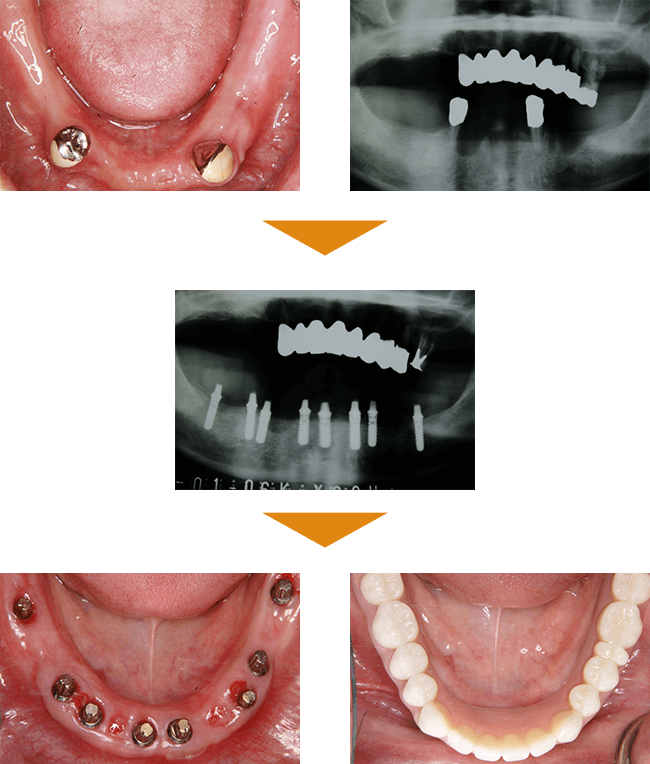

症例と経年後の状態紹介

| 治療本数 | 上顎:5本 下顎:8本 |

| 治療期間 | 8カ月 |

| 費用 | 合計 6,500,000円(税込) |

BEFORE

この患者様の治療には、初診から最終補綴物装着までに約半年の治療を要しました。当時、最先端といわれていた治療も併用して、治療に臨みました。

患者様は、相当な額の治療費をお支払いくださり、最後まで根気よく受診してくださいました。

AFTER

最終補綴物装着の日に、患者様に「治療は、今日から始まりですよ。」と伝えると、『今日で終わりではないのか?』という不思議そうな表情をされていらっしゃいました。